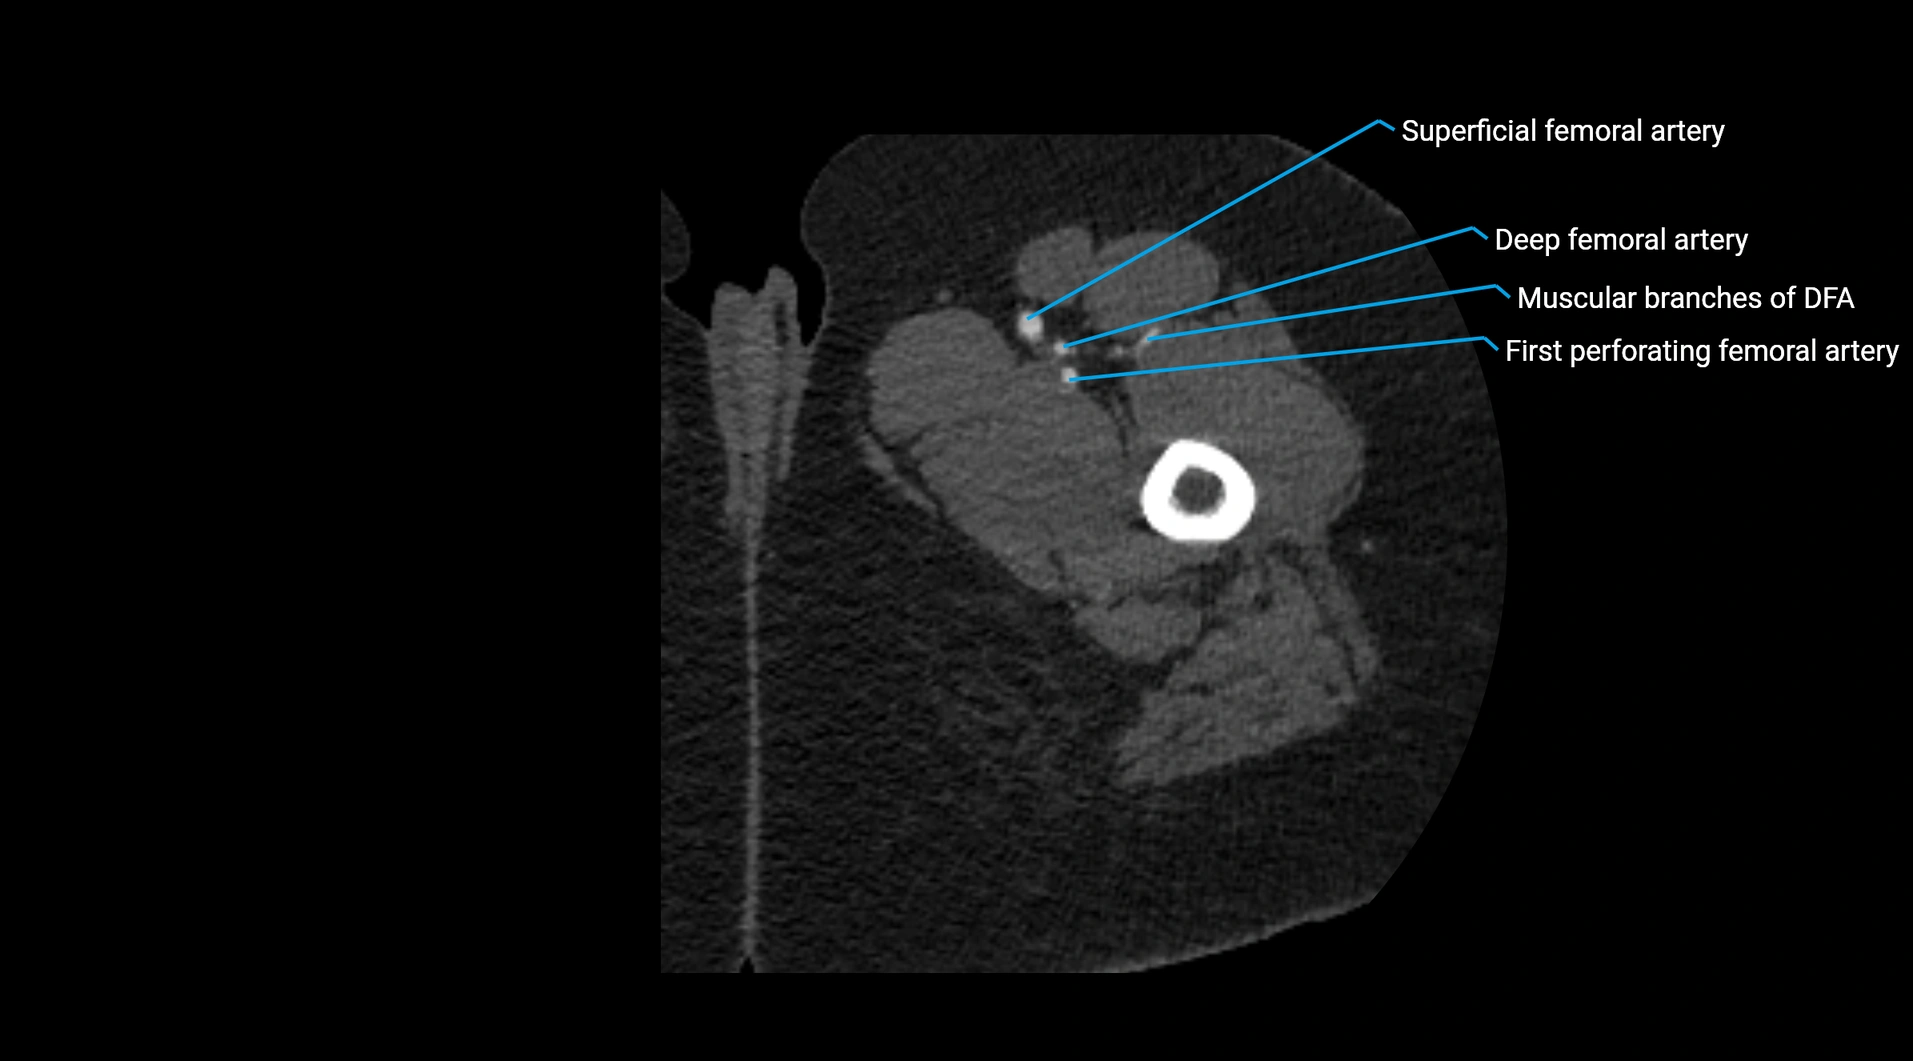

CT Appearance

Non-contrast CT:

• Appears as a tubular soft tissue structure anterior to vertebral bodies

• Calcified atherosclerotic plaques appear as hyperdense foci along the wall

• Useful for screening abdominal aortic aneurysm (AAA) size and mural calcification

Contrast-enhanced CT (CTA):

• Gold standard for abdominal aortic imaging

• Provides excellent detail of lumen, wall, aneurysm, thrombus, and branch vessels

• Multiplanar and 3D reconstructions help in aneurysm measurement, stent graft planning, and dissection evaluation

• Detects acute rupture, traumatic injury, or occlusion with high sensitivity

CT images

image